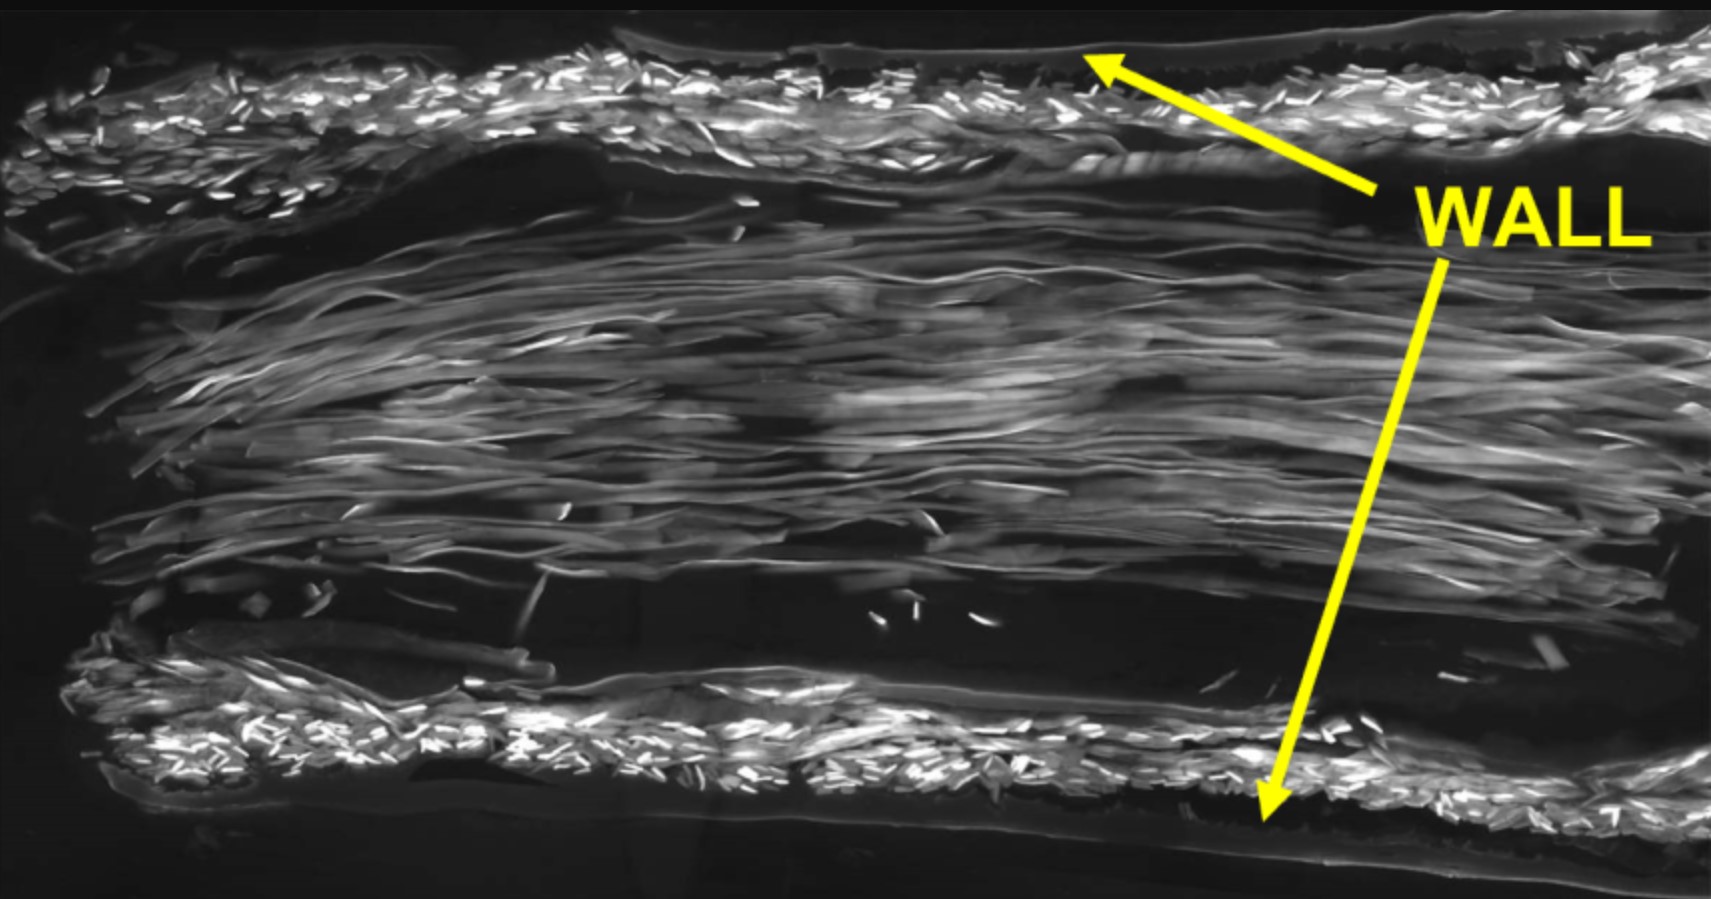

В новом исследовании исследовательская группа разработала новый тип нервного проводника с использованием двух разных типов натурального шелка. Стенка трубки была изготовлена из шелка шелкопряда (Bombyx mori), а внутренняя часть заполнена шелковыми волокнами золотых пауков-кругопрядов (Trichonephila edulis). Трубки были протестированы на крысах, у которых был перерезан правый седалищный нерв с образованием зазора в 10 мм (значительная длина для крысы). Исследователи обнаружили, что поврежденные нервы адаптировались к новым шелковым нервным проводникам и росли вдоль шелковых нитей до тех пор, пока разорванные окончания успешно не соединились.

Исследовательская группа использовала передовые методы микроскопии для детального анализа процесса заживления. Это показало, что шелковые трубки имеют очень пористую структуру; важная функция для регенерации нервов, поскольку это позволяет обмениваться питательными веществами и отходами.